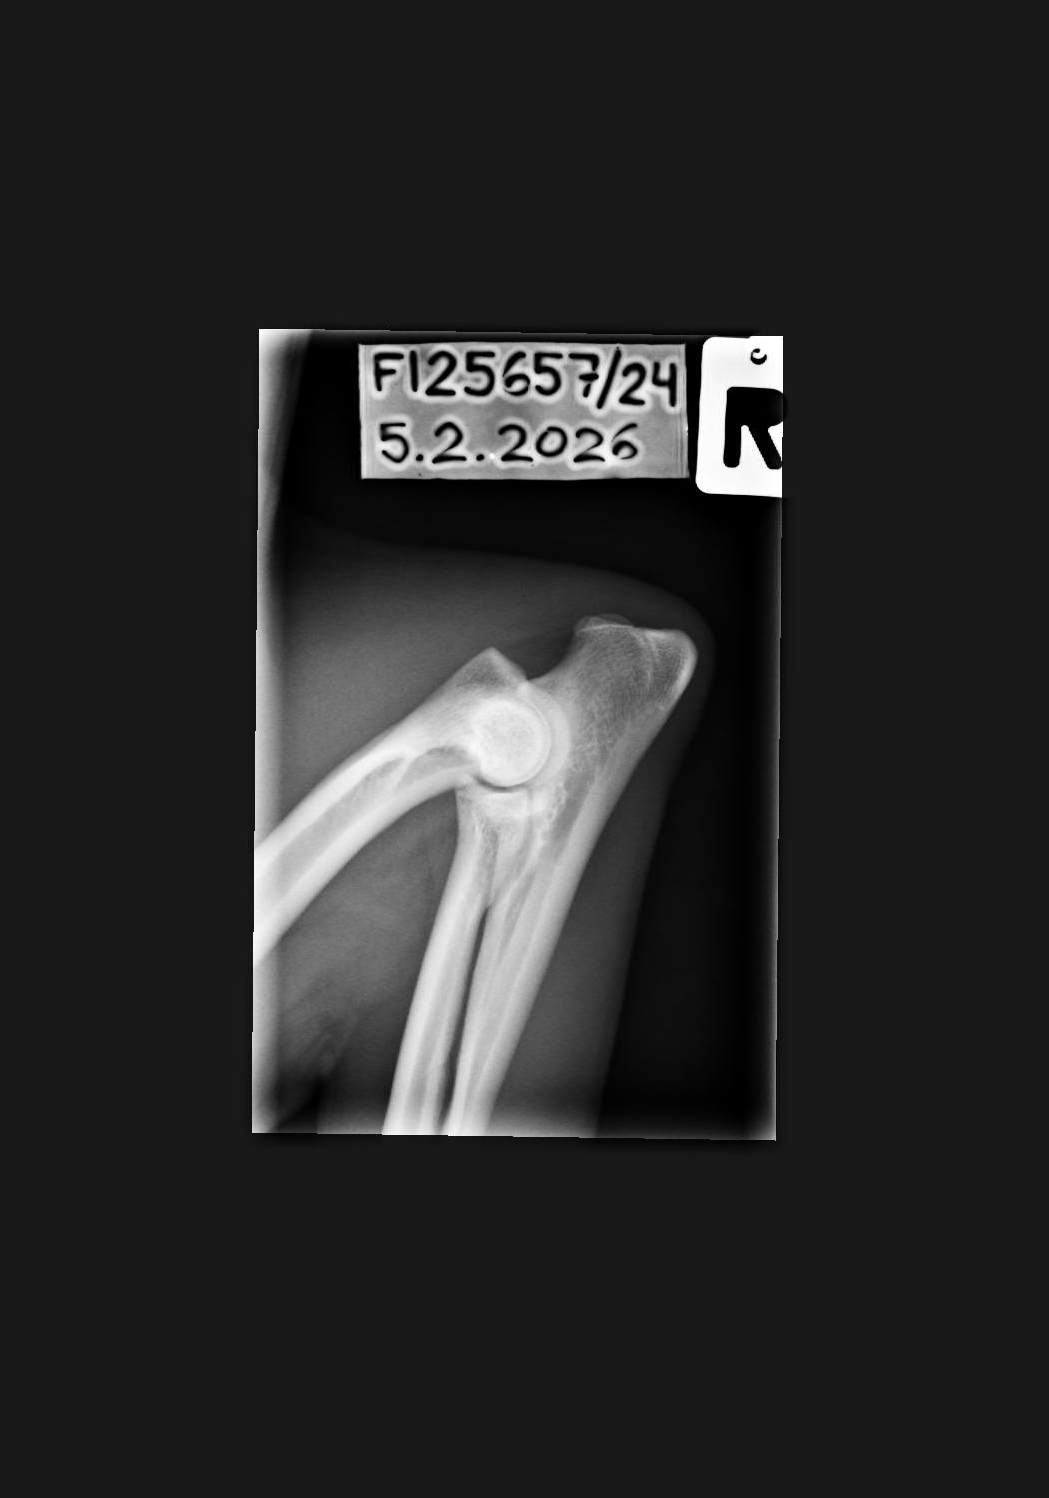

NHAT Pihlajamäen Aslan ♂ Personal

C/B |

1/0 (see Notes) |

- Finnish Kennel Club's elbow x-ray report Dec '25: Signs suggestive of medial coronoid disease; further information about the condition of the joints can be obtained, if necessary, by computed tomography (CT) examination

- Finnish Kennel Club's elbow CT report Feb '26: A small amount of new bone formation around the medial coronoid process of the left elbow